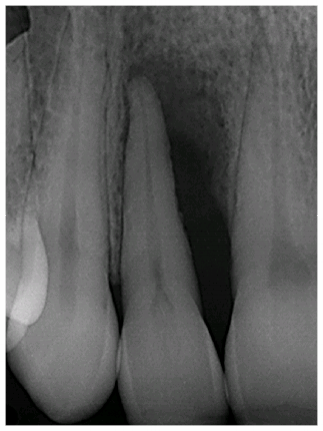

Before After

Great result of Perioscopy demonstrating before and after X-ray of the lower incisor. Initially this patient presented with a deep periodontal pocket, but only after one session of Perioscopy, a notable bony refill was evident on X-rays. Clinically his pockets reduced to 4 mm, and the patient was pleased to be able to save his tooth.